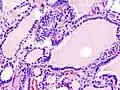

Hyperthyroidism is one of the most common endocrine conditions affecting older domesticated housecats. In the United States, up to 10% of cats over ten years old have hyperthyroidism.[59] The disease has become significantly more common since the first reports of feline hyperthyroidism in the 1970s. The most common cause of hyperthyroidism in cats is the presence of benign tumors called adenomas. 98% of cases are caused by the presence of an adenoma,[60] but the reason these cats develop such tumors continues to be studied.

The most common presenting symptoms are: rapid weight loss, tachycardia (rapid heart rate), vomiting, diarrhea, increased consumption of fluids (polydipsia), increased appetite (polyphagia), and increased urine production (polyuria). Other symptoms include hyperactivity, possible aggression, an unkempt appearance, and large, thick claws. Heart murmurs and a gallop rhythm can develop due to secondary hypertrophic cardiomyopathy. About 70% of affected cats also have enlarged thyroid glands (goiter). 10% of cats exhibit "apathetic hyperthyroidism", which is characterized by anorexia and lethargy.[61]